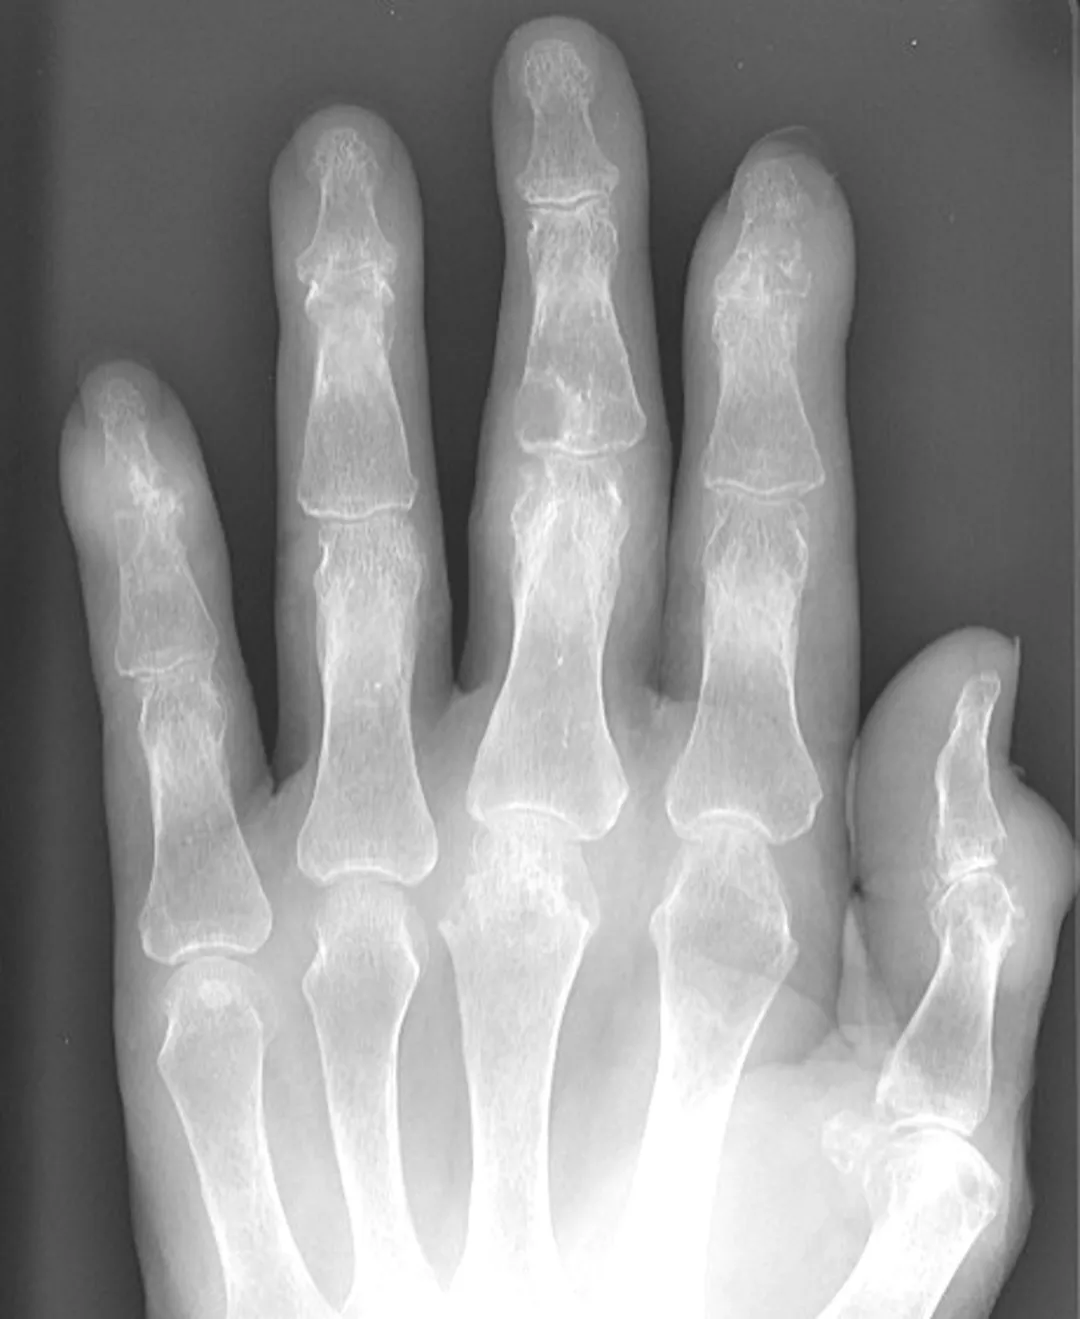

身体診察ではBMI 28、図1に右手の所見を示す(両手指に多関節炎を認める)。(図1)頭皮に鱗屑を伴う軽度掻痒感をみとめる皮疹を認めた。爪病変なし。

図 1 右手

所見︓右 1MCP/IP 関節、2MCP・PIP 関節、3MCP 関節に関節炎あり